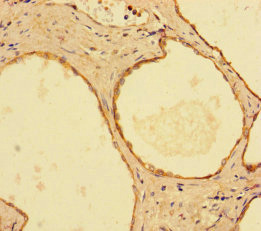

Immunohistochemistry of paraffin-embedded human prostate cancer using CSB-PA01195A0Rb at dilution of 1:100